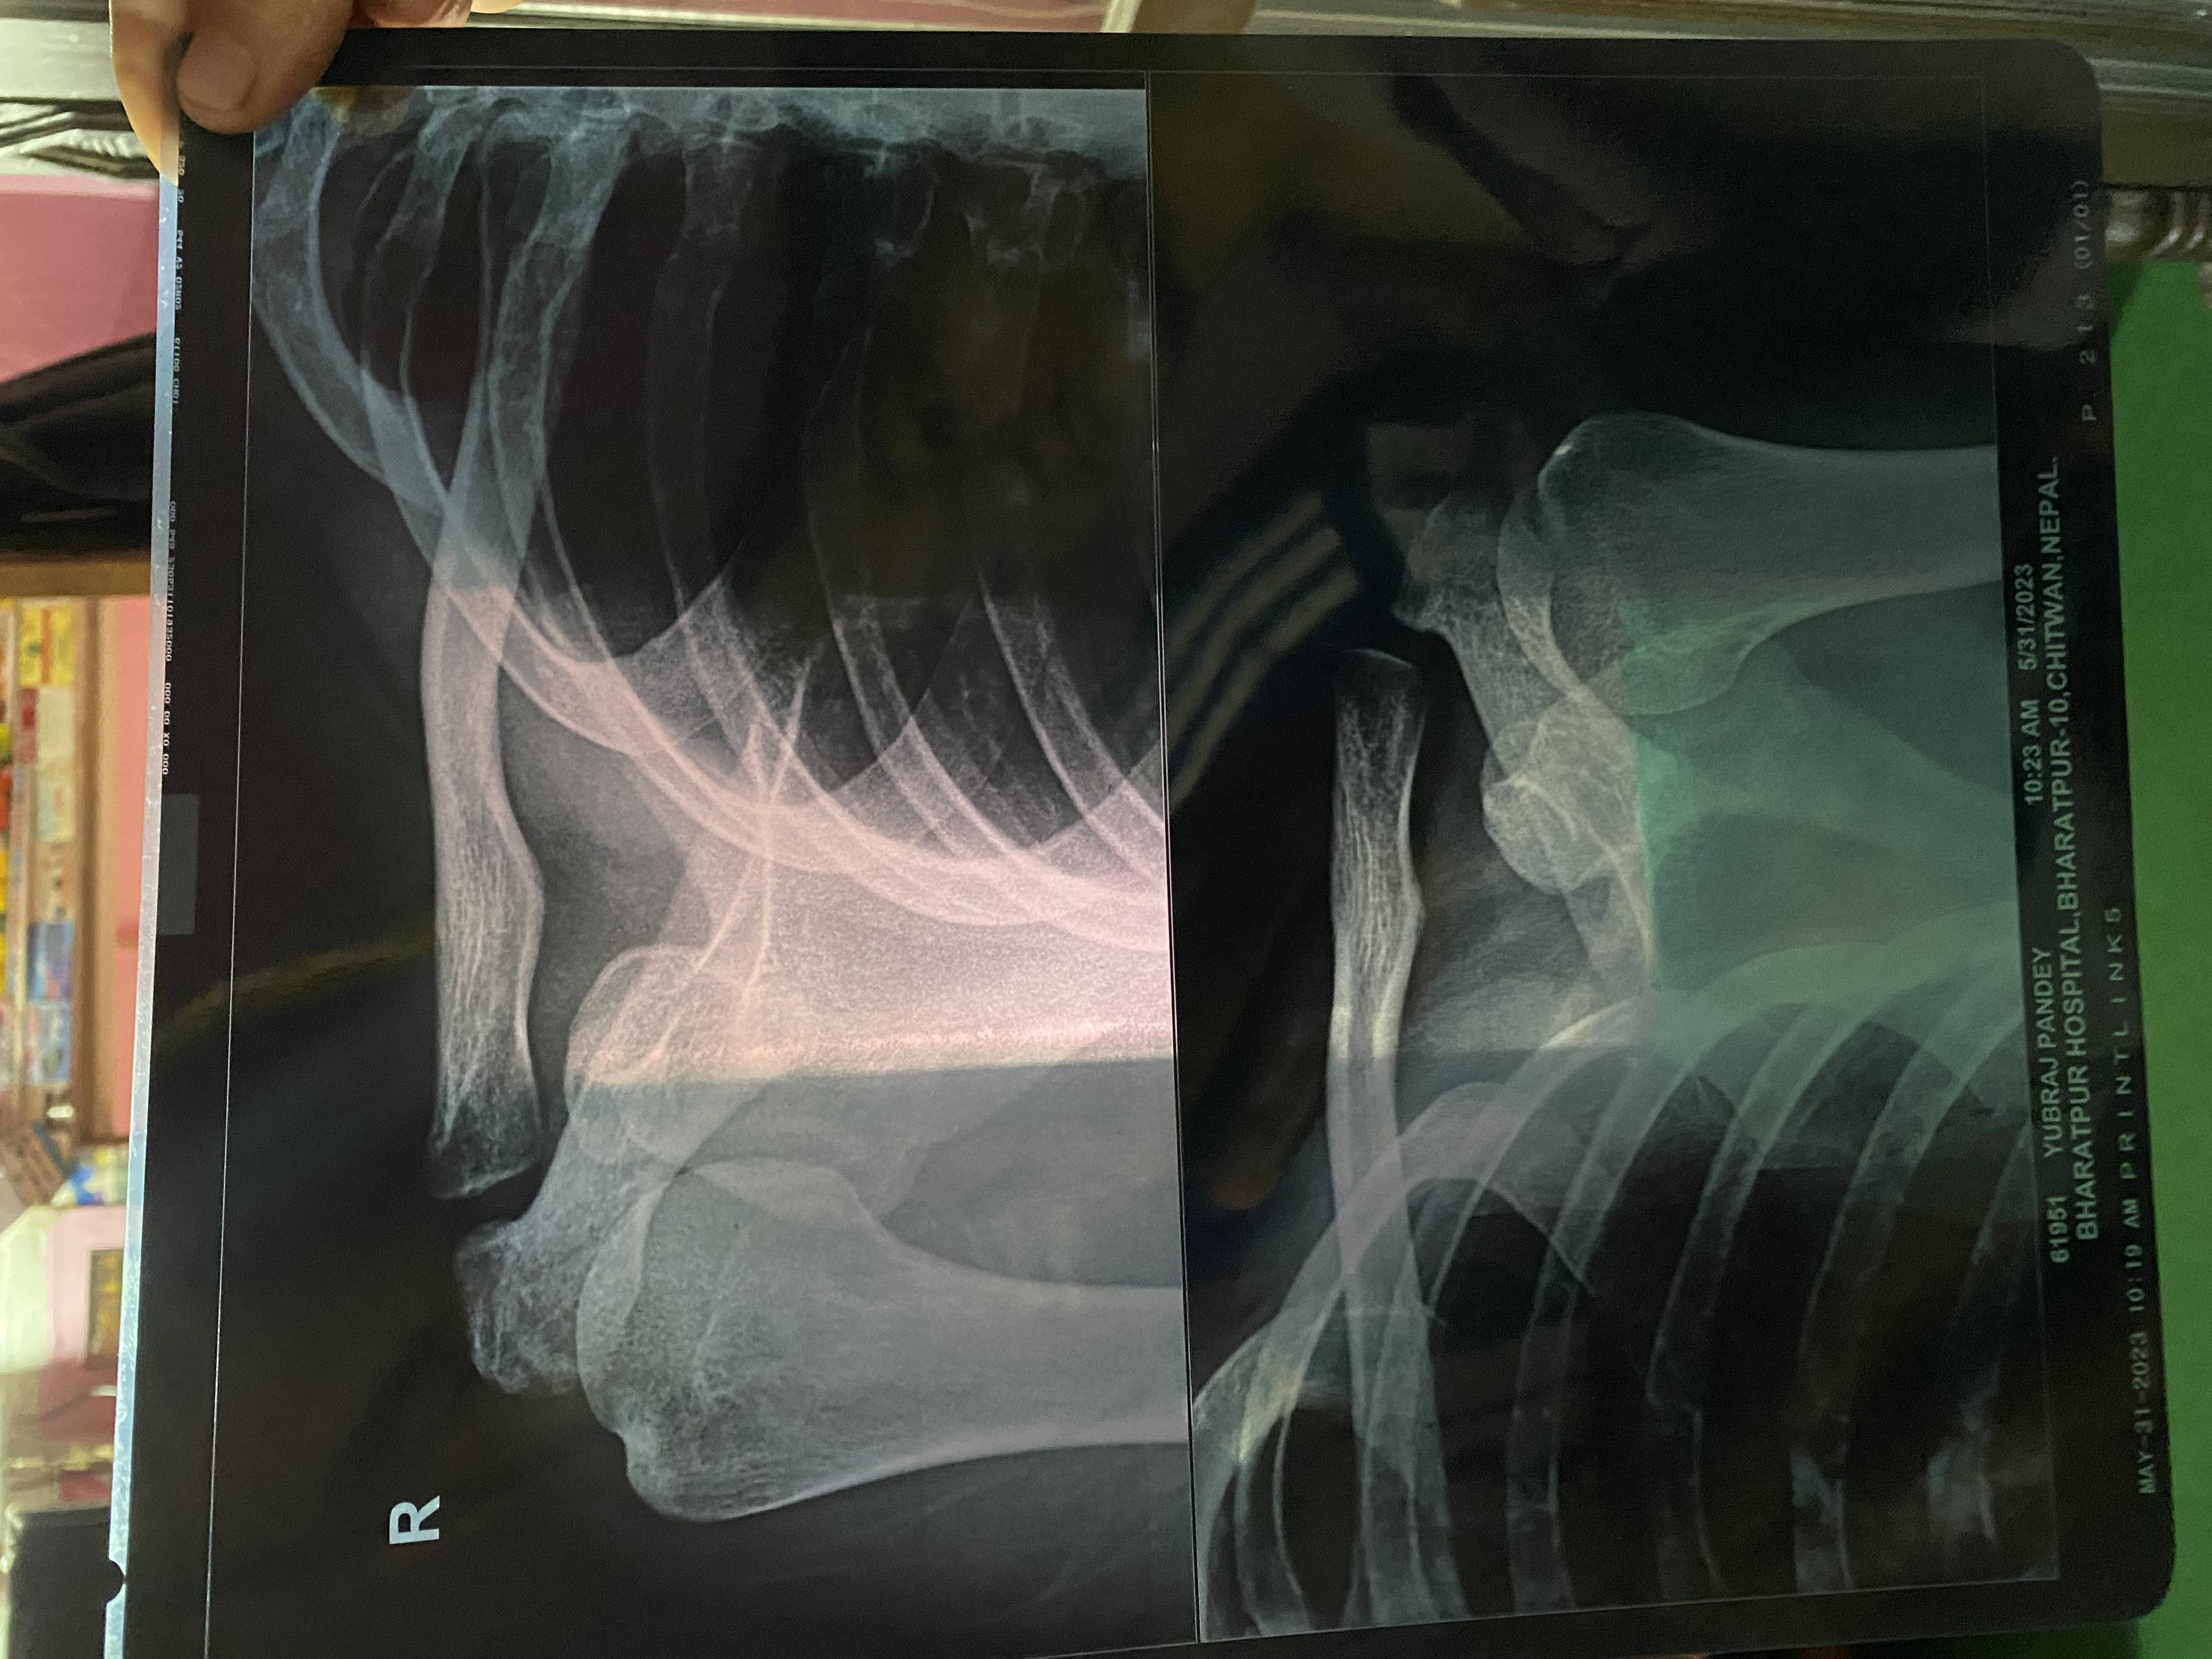

Name: Yubaraj Pandey

Yubaraj Pandey

I have pain in my left shoulder Can you find out what's the problem ?

Here are x-rays of 2 different dates and inform me after complete

reason of accident (Fallen From Tree)